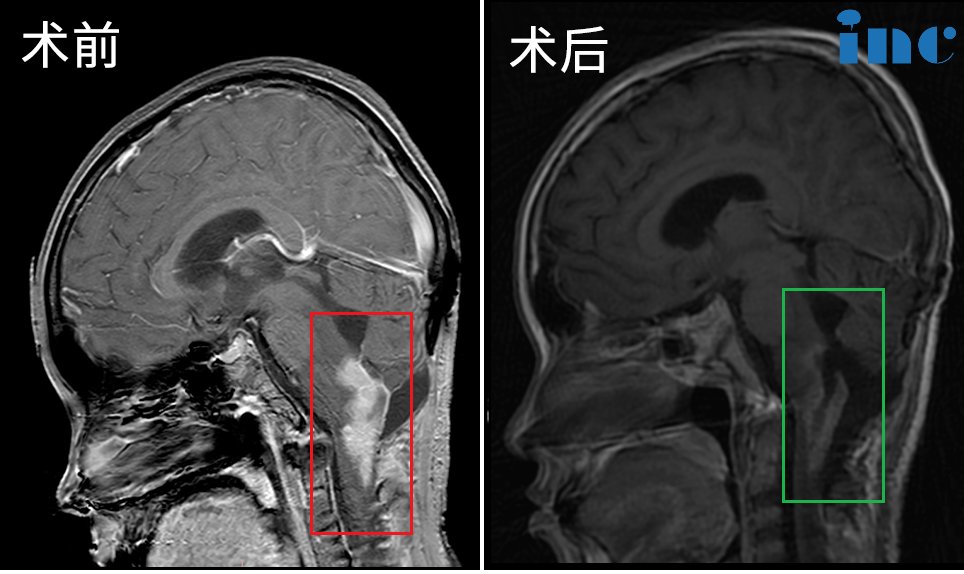

▼34岁男性-脑干延髓胶质瘤

▼30岁女性-脑干海绵状血管瘤